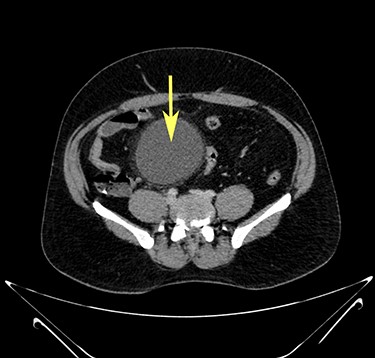

Computerized tomography showed a solitary well defined intraperitoneal cyst consisting of fluid showing low attenuation. The wall of the cyst was 1 cm thick, with no contrast enhancement. It was situated in the pelvis compressing the urinary bladder. It had no communication with either the bowel or the urinary bladder. The pancreas was normal, as also the rest of the abdominal organs. There was no ascites (Figs. 1–5). The diagnosis was a large intraperitoneal infected cyst.

Transverse section image of a contrast-enhanced CT scan of the abdomen at the level 4–4 (Fig. 1), showing a solitary cyst (C) with a non-enhancing wall separate from the urinary bladder (B). Iliac vessels are labelled with arrowheads.